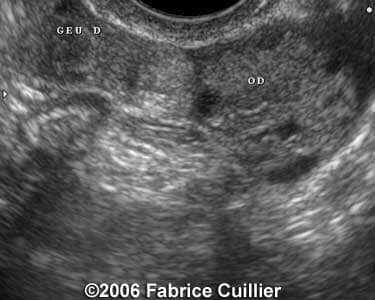

These are some cases of ectopic pregnancy (GEU) using the 2D and 3D scans.

Case 3